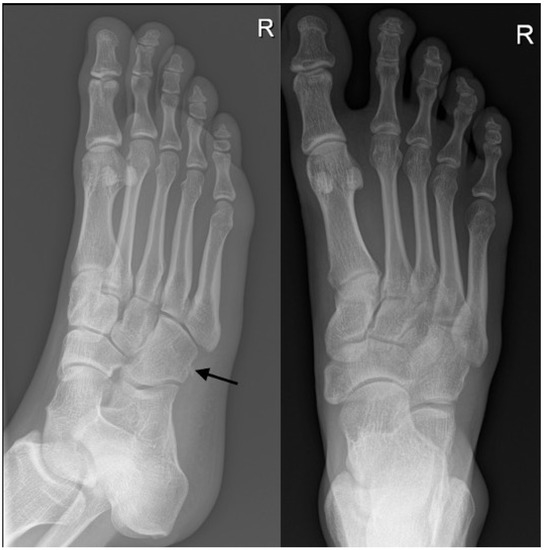

Figure 2. An example of a radiograph that was categorized as accurate. A foot radiograph was performed on a 56-year-old male with a history of falls. Both the trainee and radiologists agreed on there being cuboid fracture with chip bone fragment (black arrow).